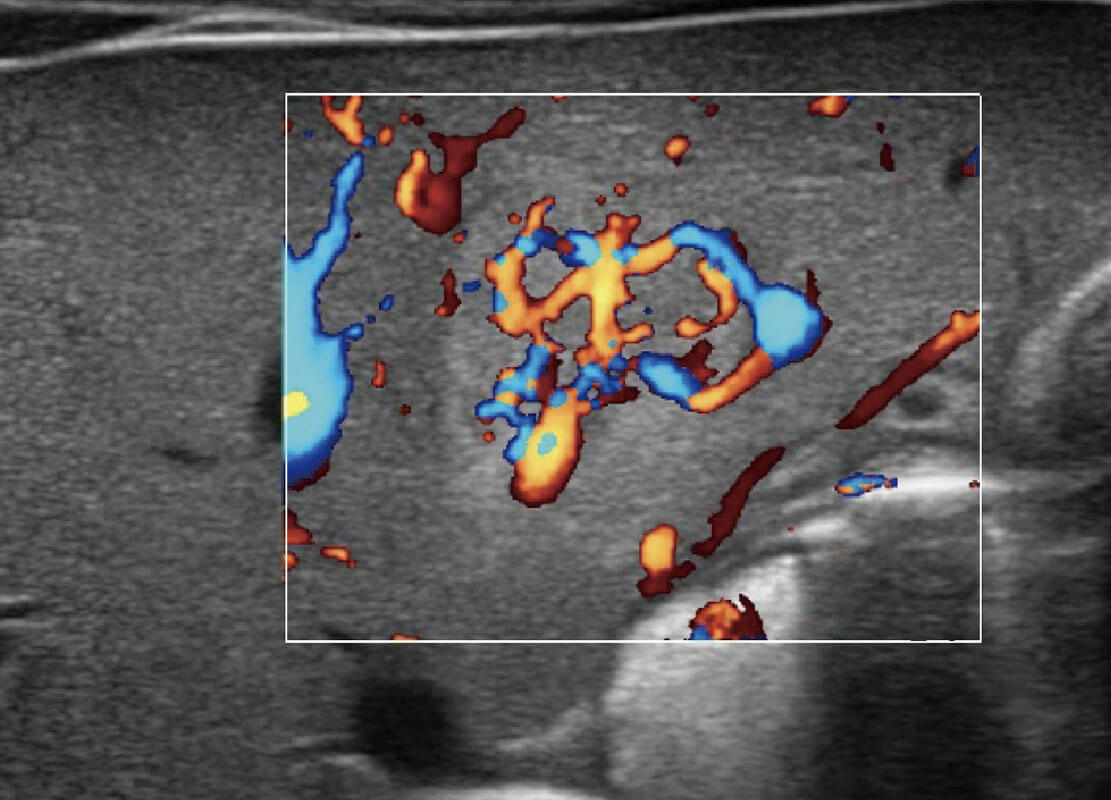

P60搭载宽频带线阵探头、宽景成像、弹性成像技术,为您提供乳腺应用方案。P60支持高频相控阵探头、线阵探头、腹部高频探头、腹部微凸探头等,丰富的探头群搭载敏感的彩色血流成像,适用于新生儿多种脏器检测要求,满足新生儿筛查需求。

乳腺癌显微血流